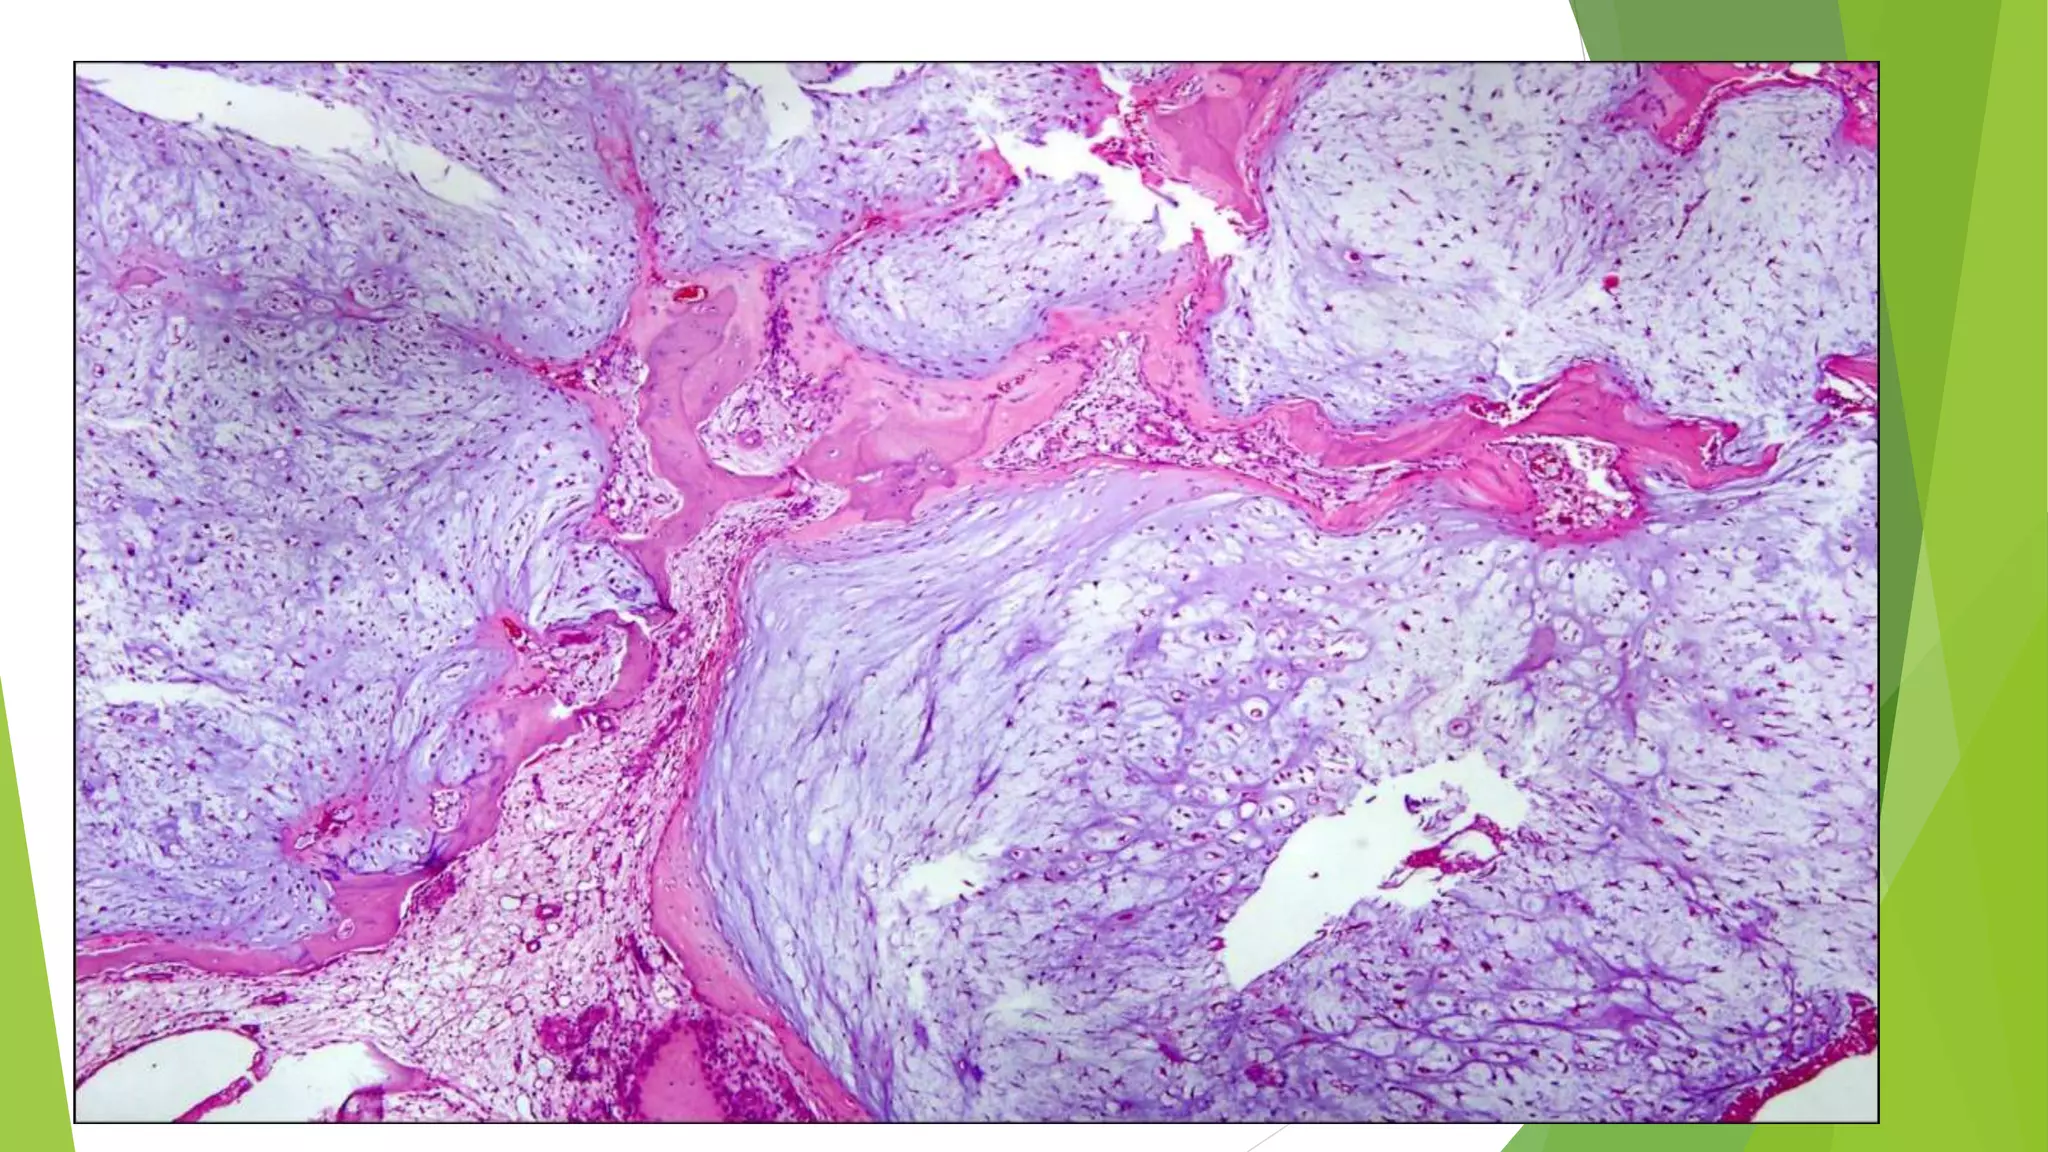

GROSS

 Spongy, hemorrhagic mass covered by thin shell of reactive bone

MICROSCOPICALLY

 Large cystic spaces filled with blood and separated by fibrous septa,

alternating with solid areas

 Cysts and septa lined by fibroblasts, myofibroblasts and histiocytes

but not endothelium

 Clusters of osteoclast-like multinucleated giant cells with loose

spindly stroma to cellular stroma, reactive woven bone, degenerated

calcifying fibromyxoid tissue

 Variable mitotic figures and hemosiderin

 No malignant osteoid, no atypia